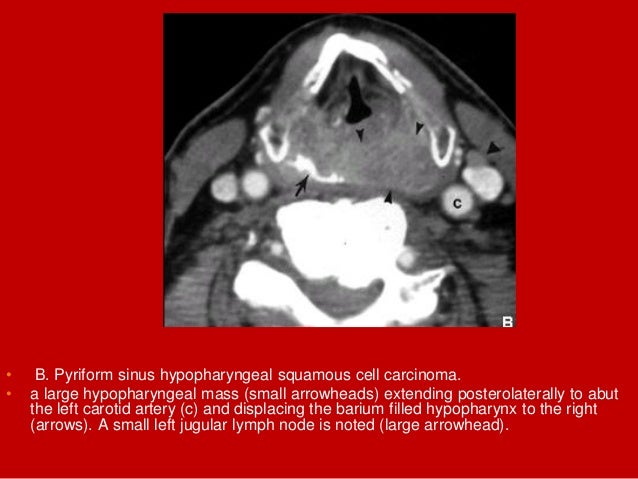

69. 69. • B. Pyriform sinus hypopharyngeal squamous cell carcinoma. • a large hypopharyngeal mass (small arrowheads) extending posterolaterally to abut the left carotid artery (c) and displacing the barium filled hypopharynx to the right (arrows). A small left jugular lymph node is noted (large arrowhead).